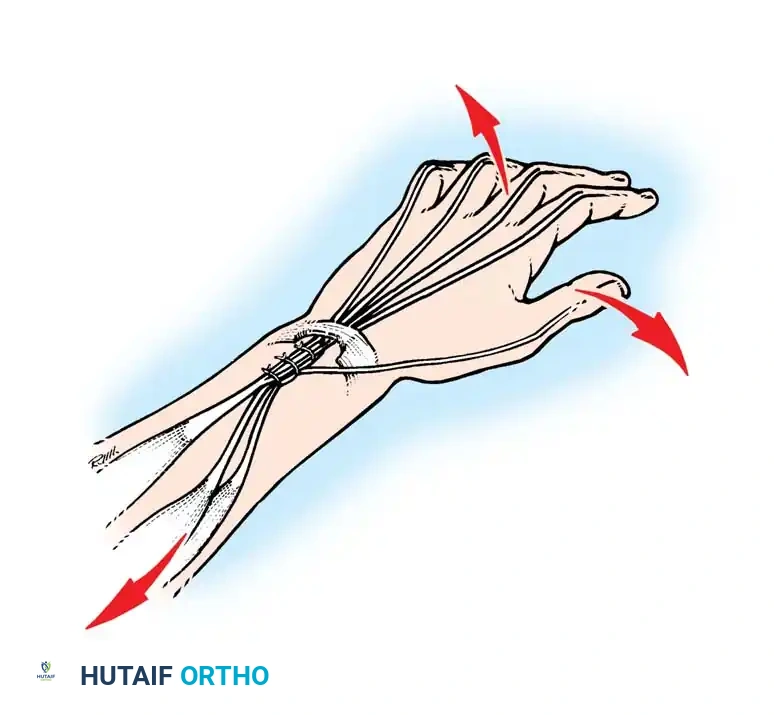

- Brachioradialis (BR) to FPL Transfer: The BR is an excellent donor for the FPL. It has immense power and adequate excursion. The BR must be mobilized extensively, proximal to the elbow joint, to maximize its amplitude.

- ECRL to FDP Transfer: If the ECRB is strong enough to maintain wrist extension independently (Group 3), the ECRL can be transferred to the Flexor Digitorum Profundus (FDP) tendons to provide active, powerful finger flexion for a full grasp.

Intrinsic Balancing and the Zancolli Lasso

Tetraplegic hands are inherently "intrinsic-minus," leading to clawing of the fingers (hyperextension of the MCP joints and flexion of the IP joints). This posture defeats the tenodesis effect, as the fingers roll up into the palm rather than sweeping in a wide arc to grasp objects.

To correct this, the Zancolli lasso procedure or similar intrinsic stabilizations are performed. The Flexor Digitorum Superficialis (FDS) tendons are divided distally, looped around the A1 or A2 pulleys, and sutured back onto themselves. This creates a static volar tenodesis that prevents MCP hyperextension, ensuring that proximal pull on the FDP translates into a functional sweeping grasp.